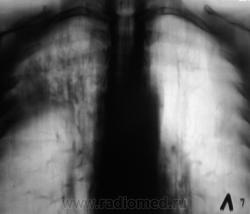

Пациент 4 месяца, по полной программе отлежал в областной конторе, ЦВК утвердило «инфильтративный». После выписки был направлен под надзор фтизиатра по месту жительства. Ниже иллюстрации после выписки.

Снимки сегодня.

Хорошая динамика, практически все рассосалось.

На мой взгляд на "семерке" еще дай-дай...